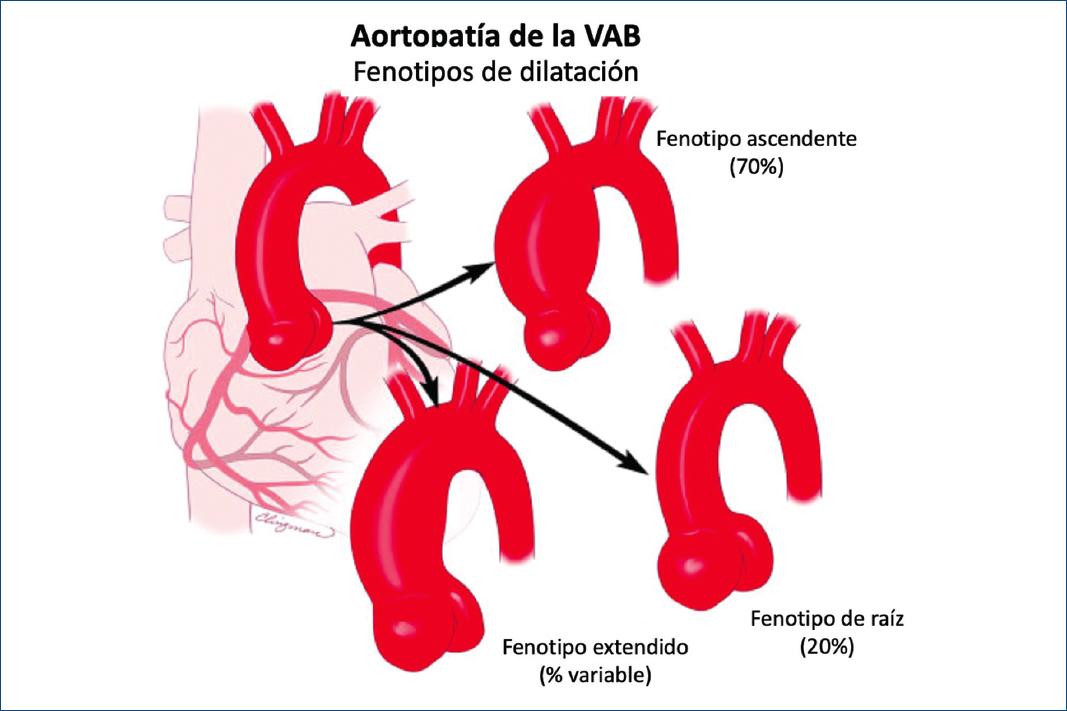

FENOTIPOS AORTOPÁTICOS DE LA VÁLVULA AÓRTICA BICÚSPIDE

La importancia de reconocer los fenotipos aortopáticos de la VAB es que su presencia y asociación con fenotipos valvulares específicos y patrones de disfunción pueden implicar diferente evolución clínica para un paciente con VAB49. Existen dos formas principales de fenotipos de VAB de dilatación aórtica: a) el fenotipo ascendente (dilatación ubicada preferentemente en el tracto tubular ascendente más allá de la STJ) (Fig. 15), que representa aproximadamente el 70% de los casos de aortopatía por VAB, y b) el fenotipo de raíz (dilatación preferentemente localizada en la raíz [senos de Valsalva]), que representa aproximadamente el 20% de los casos de aortopatía por VAB (Fig. 15)6,40,41,50. Es importante destacar que el fenotipo de raíz puede tener una dilatación ascendente leve, pero prevalece significativamente en la raíz, y el fenotipo ascendente puede tener una dilatación leve de la raíz, pero prevalece significativamente en la porción ascendente. Además, estas dos categorías a menudo corresponden a dos fenotipos generales de pacientes claramente distintos: en general, el paciente adulto o adulto mayor con VAB, ya sea hombre o mujer, que presenta con esclerosis/estenosis de la válvula aórtica (fenotipo ascendente) de una VAB de fusión derecha-no coronaria, y el paciente más joven con VAB, generalmente de sexo masculino, que presenta insuficiencia aórtica de grados que van de leve a grave (fenotipo de raíz) con VAB de fusión derecha-izquierda40,51,52. Sin embargo, esas asociaciones no son inequívocas, y la VAB con fusión derecha-izquierda puede asociarse con cualquiera de los fenotipos aórticos52. El fenotipo de raíz se ha asociado con mayor riesgo de disección aórtica aguda en el seguimiento postoperatorio de pacientes con VAB que se habían sometido a un reemplazo simple de la válvula aórtica en comparación con el fenotipo ascendente53.

Figura 15 Fenotipos de aortopatía de la válvula aórtica bicúspide. A la izquierda se ve una aorta normal. Arriba: el fenotipo más común (aproximadamente 70%), el fenotipo ascendente es la dilatación preferente de la aorta tubular ascendente. Medio: el fenotipo de raíz implica la dilatación preferencial de la raíz, observada en aproximadamente el 20% de los pacientes con válvula aórtica bicúspide con aortopatía. Abajo: el fenotipo extendido muestra dilatación de la raíz, la aorta ascendente y el arco. Los fenotipos extendidos más comunes son raíz más aorta ascendente y aorta ascendente más arco.

Notablemente, en algunos casos la dilatación de la aorta no prevalece significativamente en un segmento específico. En una proporción de estos casos, una dilatación localizada en la primera observación puede evolucionar durante el seguimiento, con posible dilatación de segmentos adyacentes previamente normales de la aorta. En este escenario, el fenotipo ascendente puede presentarse, especialmente si hay una válvula de fusión derecha-no coronariana, con dilatación asociada del arco aórtico; es apropiado referirse a esta condición como fenotipo ascendente extendido. Del mismo modo, se ha demostrado que el fenotipo de raíz se asocia de forma independiente con un crecimiento más rápido del tracto tubular ascendente, de modo que se han observado casos de extensión de una configuración inicial del fenotipo de raíz hacia una dilatación significativa de ambos tractos (Fig. 15); fenotipo de raíz extendido sería la definición apropiada de esta forma. En el contexto de un fenotipo de raíz, la presencia y progresión de borramiento de la STJ puede ser un signo inicial de este tipo de evolución.